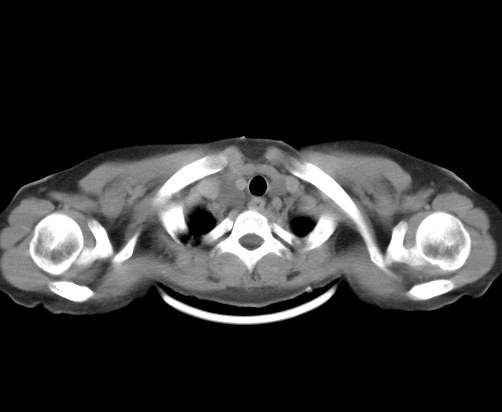

标题: CT23915:女 20岁 全身长疙瘩三年 今日多体位查 看看吧 [打印本页]

标题: CT23915:女 20岁 全身长疙瘩三年 今日多体位查 看看吧

胸部

神经纤维瘤病